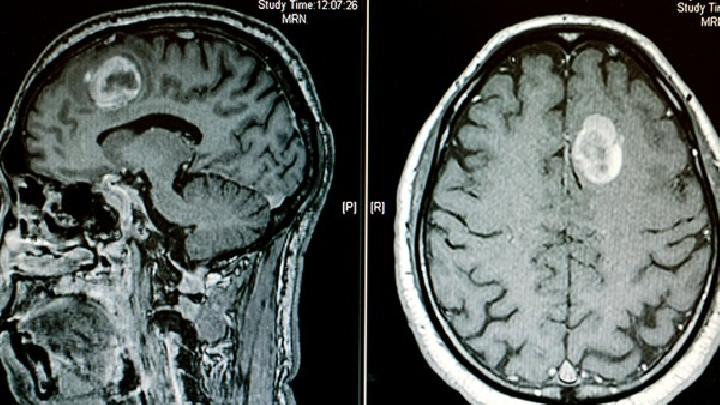

顱腦CT:主要用于明確有無器質(zhì)性病變及病變部位等。常見的異常包括廣泛性腦萎縮、腦軟化及白質(zhì)發(fā)育不良等。對于部分病例可用于提示病因,如先天性腦發(fā)育畸形、宮內(nèi)感染等。